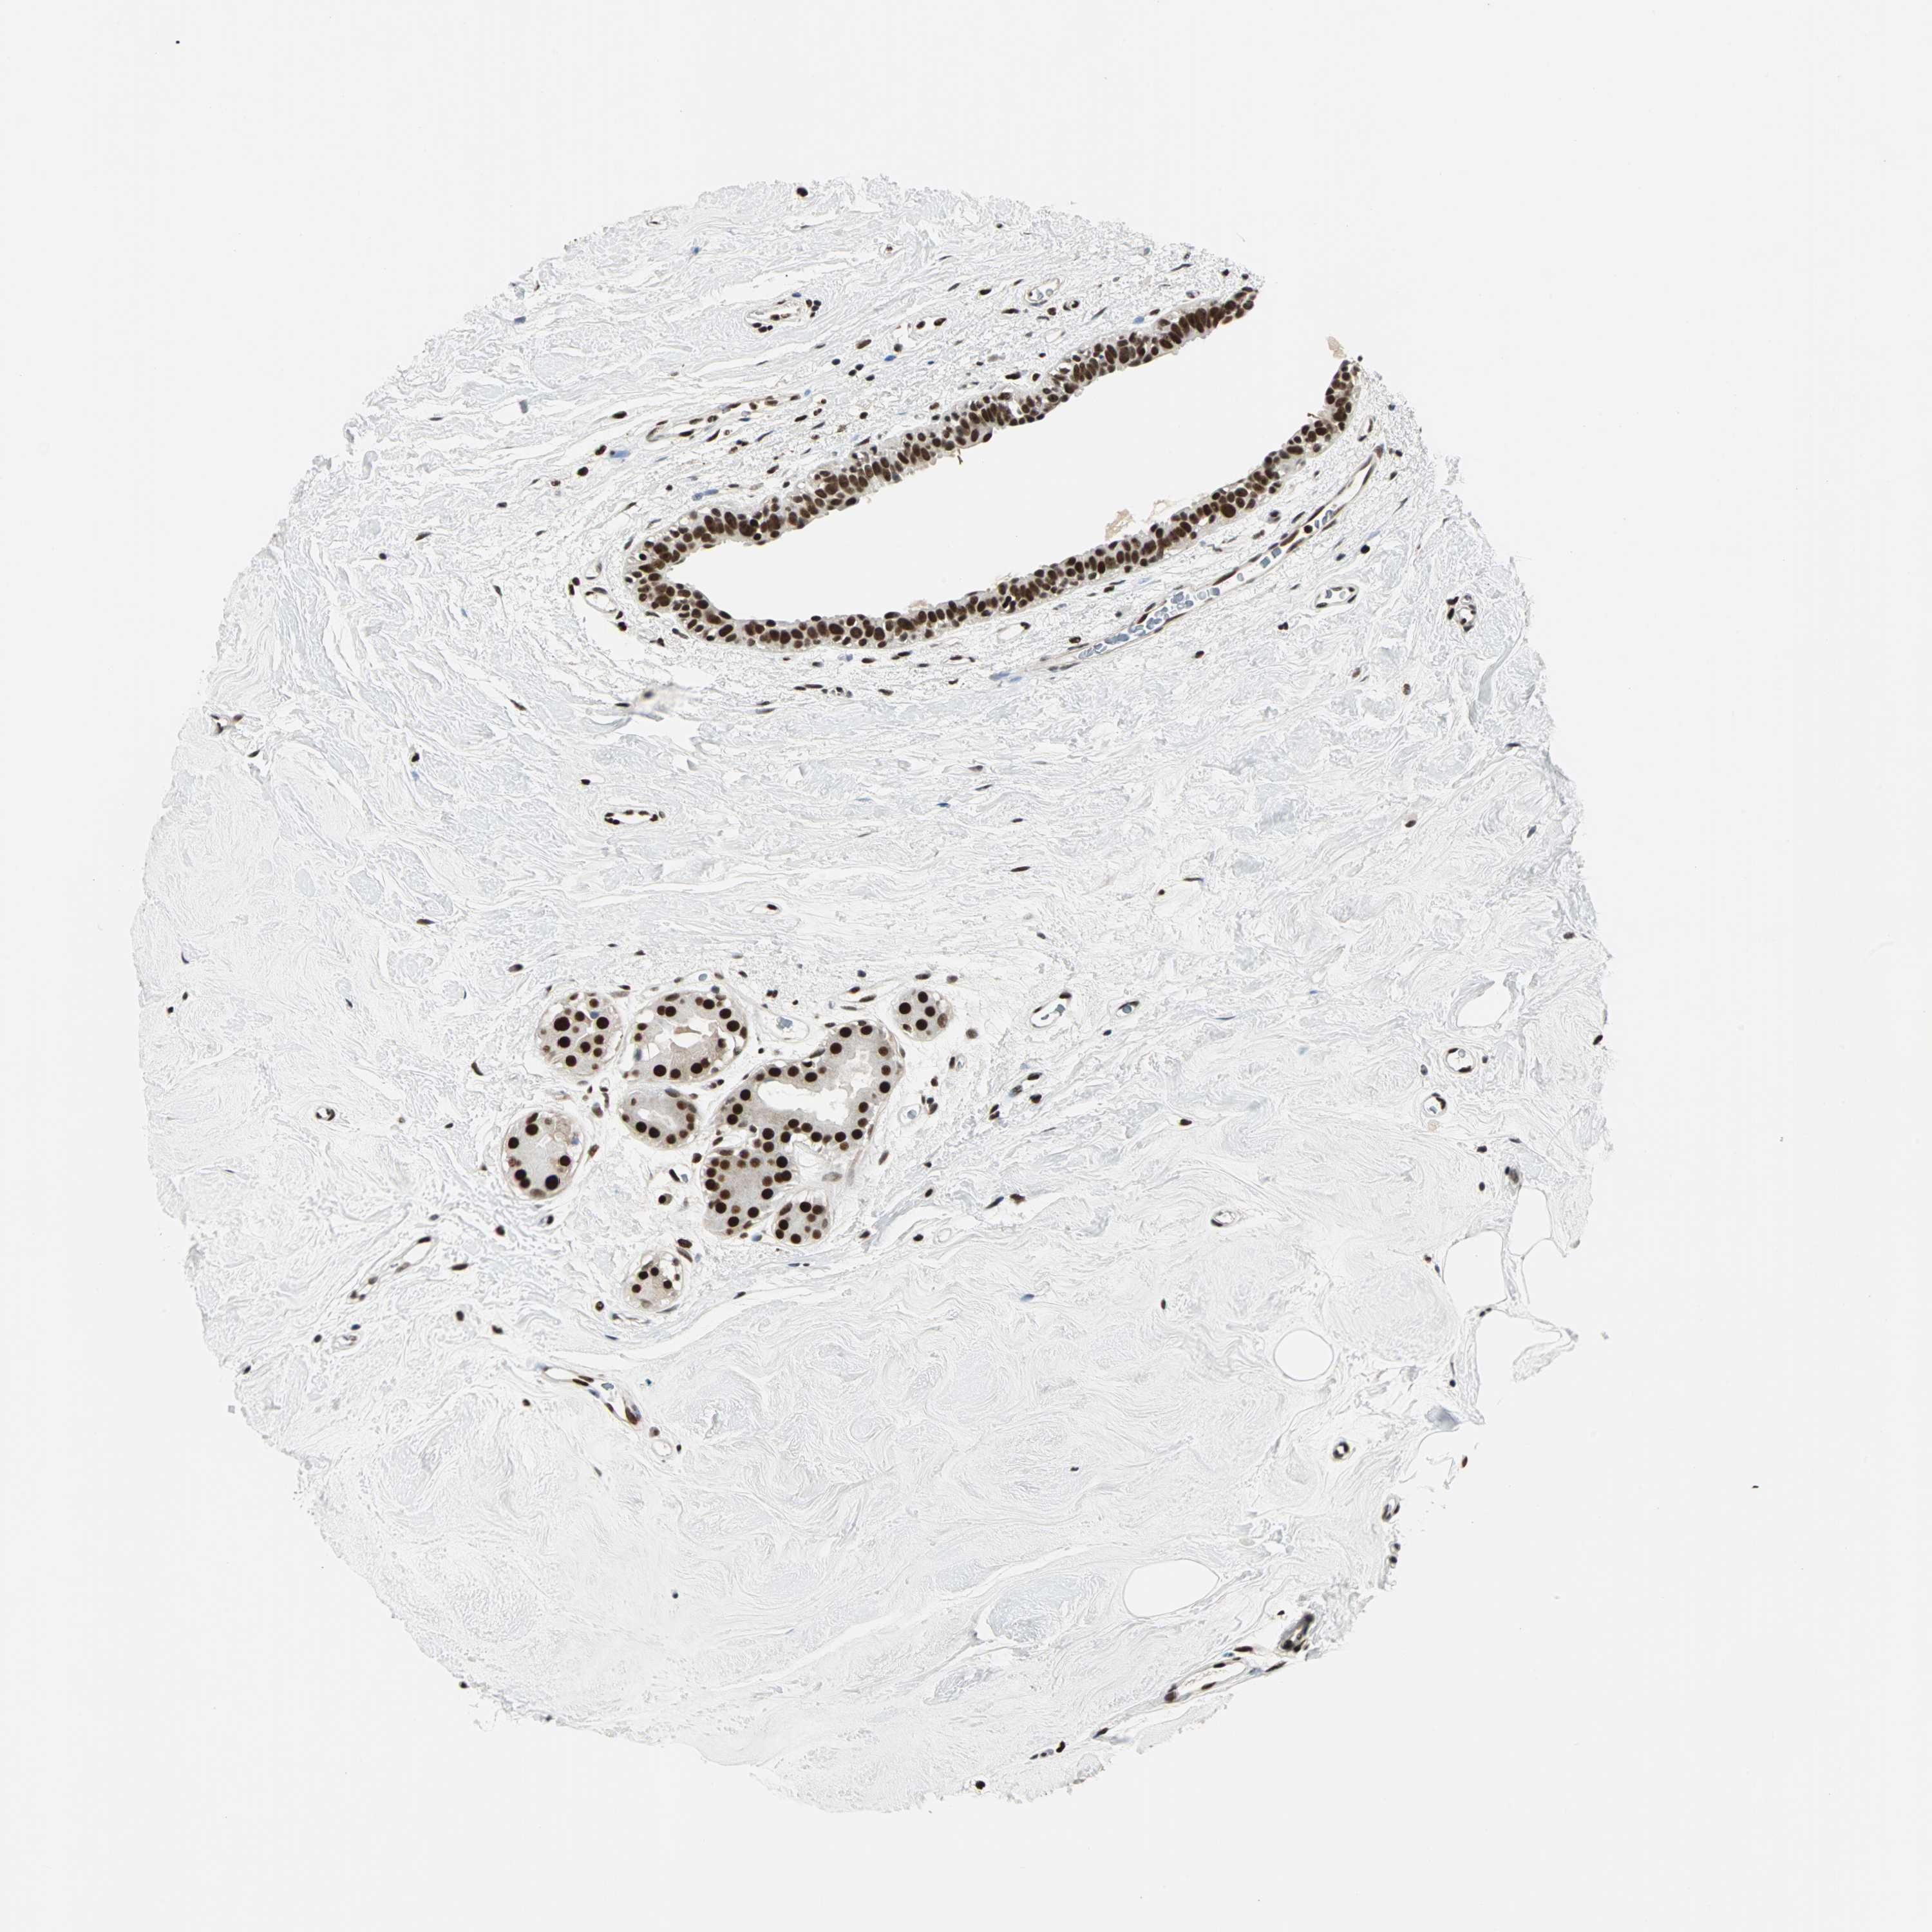

BRCA TCGA BRCA VALIDATION PROTEIN EXPRESSION

ANTIBODIES

AND

VALIDATION